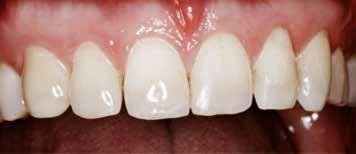

Postoperativ status

okklusal-vertikale dimension. De afficerede dentinoverflader blev ridset i overfladen med en grov diamant, men derudover blev der ikke foretaget nogen form for kavitetspræparation, da intentionen var at gennemføre en minimalt invasiv behandlingstilgang. Kofferdam blev anlagt i hvert arbejdsfelt (Fig. 3) og adhæsivet påført med en æts-og-skyl-strategi (ætsning af emalje og dentin, primer, adhæsiv). Derefter blev tænderne bygget op med en mikrohybrid komposit for at genskabe tandens naturlige form (Fig. 4). I underkæbefronten blev der kun lagt et tyndt lag med komposit pga. pladsmangel. Efter omhyggelig pudsning og polering havde patienten okklusion på samtlige tænder og var tilfreds med både funktion og æstetik.

Fig. 4. Færdigrestaurerede tænder med komposit.

Fig. 4. Final restored teeth with composite.